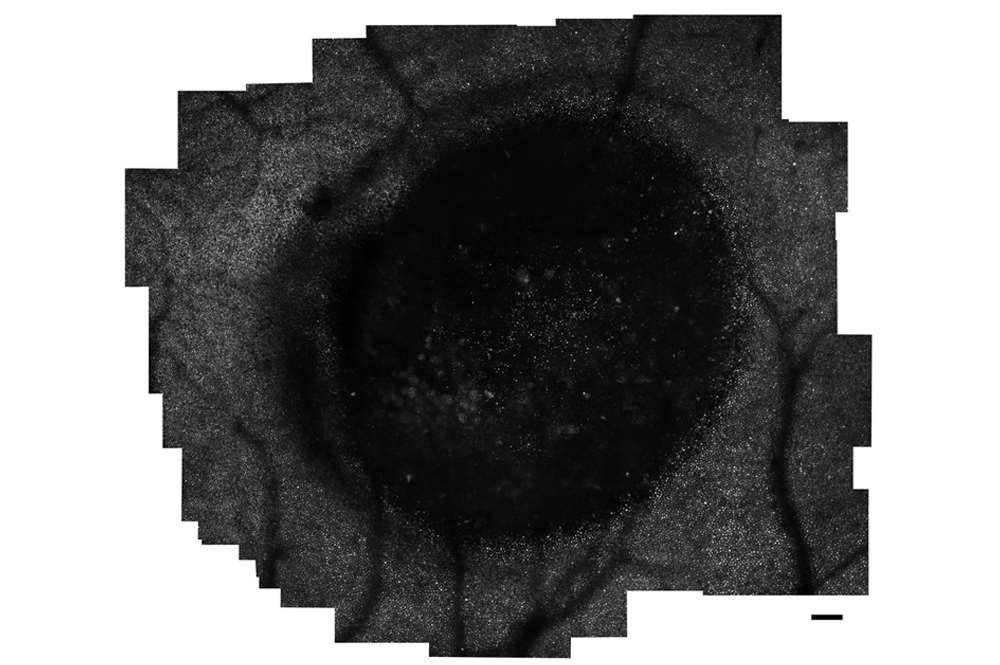

Best Disease

Shown is a montage of the foveal photoreceptor mosaic in a patient with Best disease, obtained with an adaptive optics scanning light ophthalmoscope. The large dark area aligns with a lesion seen on optical coherence tomography.